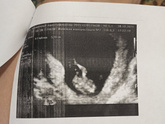

Была сегодня на узи и сдавала кровь на поталогии и бэта-хгч.

По узи всё отлично, твп хороший, носовая кость хорошая, предположили мальчика,

Но это не точно, посмотрим.

Вот фоточки ?